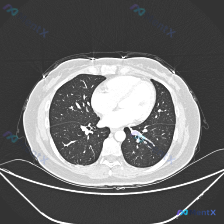

看到这份胸部CT读片资料,整理了完整的分析思路和大家分享。 病例影像基本信息 这是一份胸部CT肺窗横断面图像,层面位于心室水平,展示双侧肺下叶区域,图像质量清晰,无明显伪影影响观察。 影像核心发现 1. 双肺纹理走行自然,透亮度基本对称,双侧支气管管腔通畅,肺门结构清晰,未见肿大淋巴结;双侧胸膜光滑...